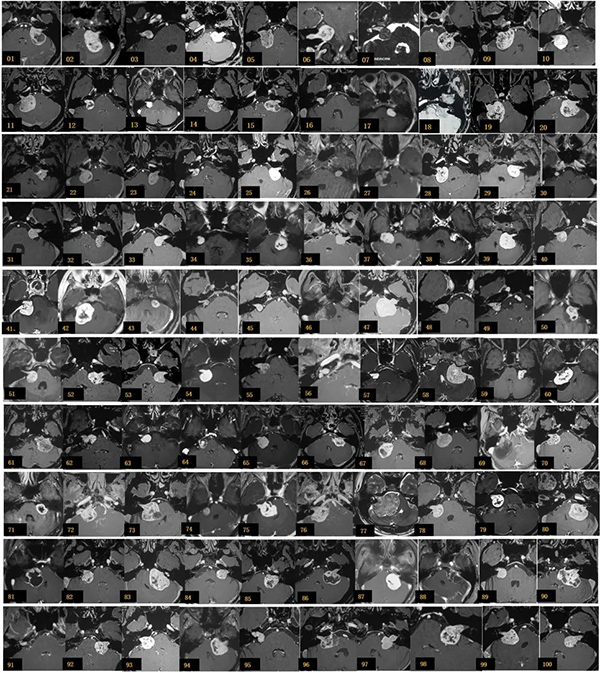

2018.12-2019.8 完成的100例听神经瘤手术